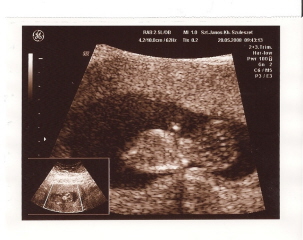

Mintha lenne valami a lábaközt, nem? :shock: A 4D felvételen se látszik van a neki kukija vagy sem?

Igen én is úgy látom, mintha lenne valami, de nem tudom, ez mennyire az, ami... (ezt jól meg mondtam :))

A 4D-n nem csinált alulról felvételt, csak oldalról, amilyet fel is raktam.

trombi én is mintha fiút látnék a képeden!!!gratula marha jó képek!

trombi. gratula, nekem is fiunak tunikl, de persze en aztan vegkepp nem vagyok szakerto :D

Hát én ,mint naagy szonográfus, a lábai között nem látok zacsit..:) Én kislánynak nézem..:)